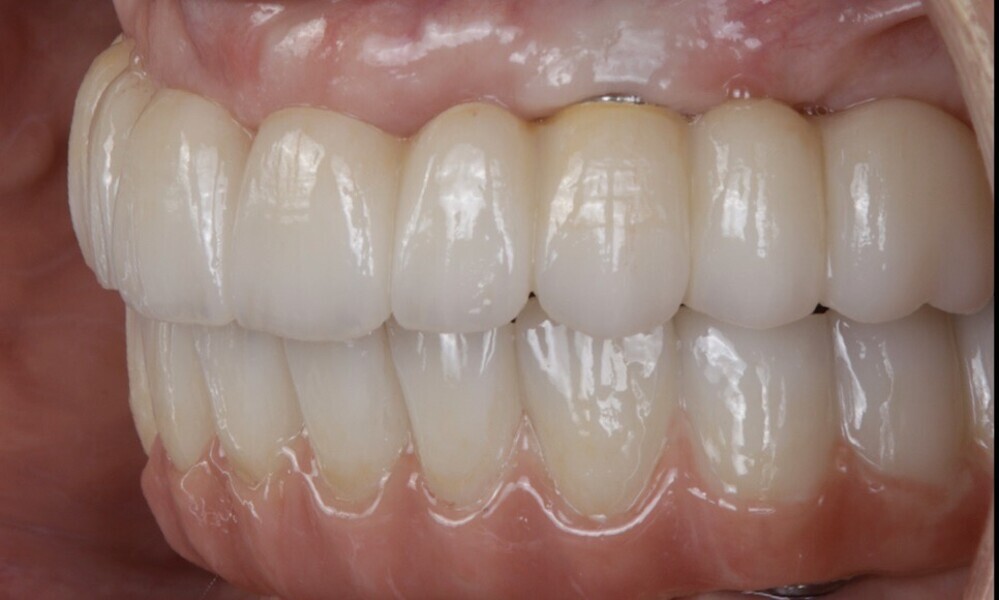

The soft tissue was in good condition, and the definitive restorations were placed (Figs. 76 & 77). After placing the definitive restorations, oral hygiene instructions were given to ensure proper care and prevent complications. Additionally, the occlusion was carefully checked and adjusted as needed (Figs. 78–83).

Figs. 78–82: The definitive restorations were placed, and occlusal adjustments were performed.

Fig. 79

Fig. 80

Fig. 81

Fig. 82